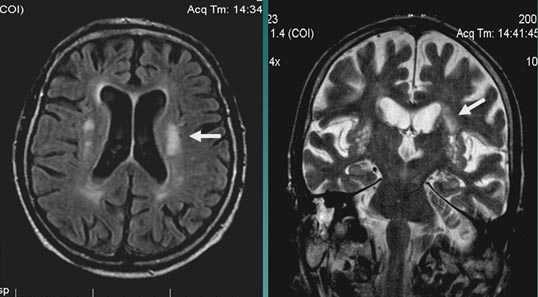

Первые часы ОНМК. Изменения в области правого островка демонстрирует только программа DW insult.

Лакунарное ишемическое ОНМК на фоне хронической сосудистой недостаточности.

Некоторые инфаркты при дисциркуляторной энцефалопатии протекают бессимптомно. Это «немые» инфаркты, которые, как правило, локализуются в глубоких отделах мозга и диагностируются только при МРТ. Этот случай показывает возможности выявление очага ограниченного ишемического ОНМК базальных ядер слева на фоне хронической ишемии.

Выраженная сосудистая энцефалопатия с наличием множественных очагов хронической ишемии, лакунарных постишемических кист. Программа ДВИ четко показывает фокус острого ОНМК в базальных ядрах справа на фоне лейкодистрофии.